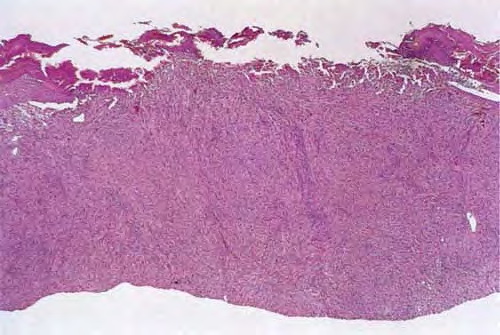

Atypical fibroxanthoma =صفروم ليفي غير نموذجي

Atypical fibroxanthoma=صفروم ليفي غير نموذجي